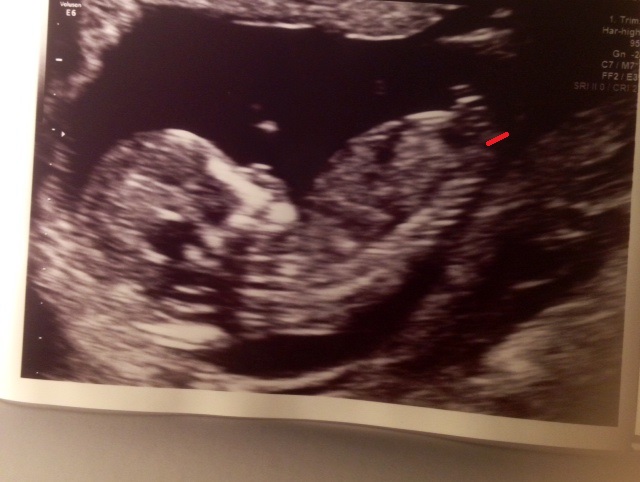

could this be the nub or just a shadow?Attachment 30040

That's too close to spine for nub I am sorry to say I think boy as I see something sticking up if I have permission I could upload your photo to edit and show you then delete your photo x

Attachment 30054

It does look very similar to my sons with the nobbly bit at the top turns out my update stopped me been able to draw on photos anyway x